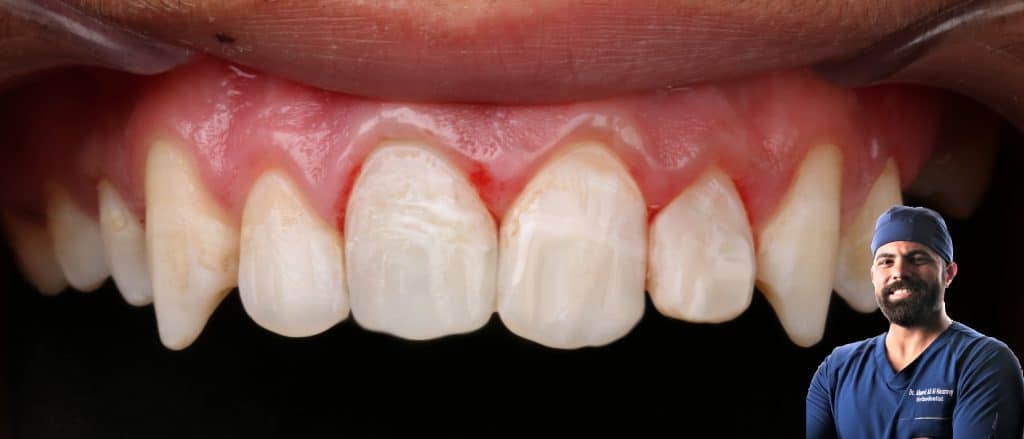

color change

loss of tooth structure

Colour change due to trauma